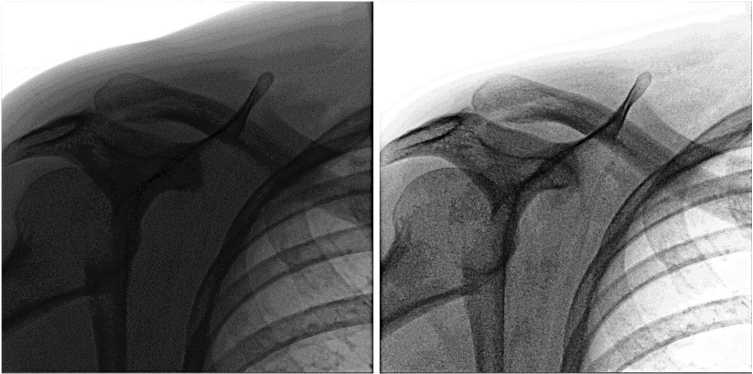

В качестве второго примера рассмотрим LUT, пригодный для плотных тканей, полученный функцией преобразования со следующими параметрами: span=.4, shift=-0.35, smoothness=0.99, strength=11.5. График функции можно видеть на рис. 3.

На рис. 4 можно видеть результат применения данного LUT. Можно заметить, что в результате такого преобразования существенно увеличивается «читаемость» костей.

Подбор параметров зависит от распределения плотности исследуемых тканей. Чем плотнее ткань, тем больше будет абсолютное значение shift (положительное для негатива). Если плотность ткани варьирует в небольшом диапазоне, то и значение span следует ограничить. Следует, однако, подчеркнуть, что для установки оптимальных значений требуется оценка эксперта.

Рис. 4. Слева – исходное изображение, справа – результат применения LUT для плотных тканей

Fig. 4. Left – original image, right – result of applying LUT for dense tissues